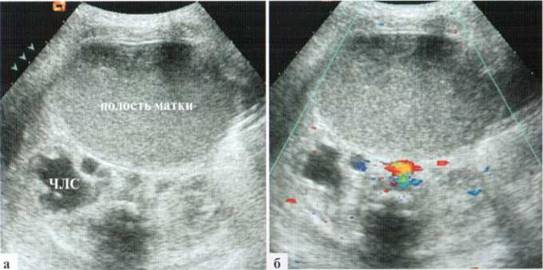

Гидрометрокольпос у новорожденных встречается редко, клинически проявления в виде «синдрома пальпируемой опухоли» в животе, иногда видна неперфорированная плева, выступающая между малыми половыми губами. При УЗИ определяется относительно толстостенное, округлой формы образование в животе, содержимое его обычное мелкодисперсной взвесью. В настоящее время, когда широко используется антенатальная ультразвуковая диагностика, достаточно часто такие новорожденные поступают в профильный стационар вскоре после рождения с направительным диагнозом «киста брюшной полости». Скопление содержимого в полости матки может достигать количества 200 мл, при этом эхографически дилатированная полость матки занимает практически весь объем живота новорожденной (рис. 2.9). Визуализировать яичники у новорожденных с гидрометрокольпос обычно не удается.

Рис. 2.9. Гидрометрокольпос у новорожденной: конвексный датчик 5 М Гц, поперечное трансабдоминальное сканирование на уровне пупка:

а — в В-режиме определяется огромных размеров отграниченная полость с четкой стенкой, мелкодисперсной взвесью в просвете;

б — в допплеровском режиме кровоток в стенке образования не прослеживается

Значительное переполнение полости матки вызывает синдром внутрибрюшного напряжения, который клинически может проявляться, в первую очередь, синдромом срыгивания и рвоты, а также — острой задержкой мочи на фоне компрессии мочевыводящих путей на инфравезикальном уровне. При УЗИ выявляется дилатация мочевыводящих путей с одной или обеих сторон, возможны резкая деформация и смещение мочевого пузыря, для отведения мочи требуется катетеризация (рис. 2.10). После операции эти изменения исчезают в течение I—2 суток.

Рис. 2.11). Дилатация чашечно-лоханочной системы (4J1C) из-за компрессии резко дилатированной полостью матки